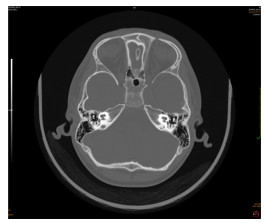

术前颞骨HRCT联合内耳MR在人工耳蜗植入患儿中的应用

武林, 贾慧惠, 陈萌萌, 顾维, 王爱平

2026, 24(1): 113-116. doi: 10.16766/j.cnki.issn.1674-4152.004342

67 2

摘要:

目的  针对重度感音神经性耳聋患儿人工耳蜗植入术(CI)中解剖结构复杂、电极植入风险高的临床难点,探讨术前颞骨高分辨率CT(HRCT)与内耳MRI多模态影像联合评估的应用价值,为优化手术方案、降低并发症风险提供影像学依据。  方法  选取苏州大学附属儿童医院2021年1月—2024年12月行CI治疗的重度或极重度感音神经性耳聋患儿192例(215患耳),对患儿行颞骨HRCT、内耳MR检查。比较2种方法对内耳畸形的诊断效能,以及电极植入异常情况;采用单因素和logistic回归分析研究电极植入异常的危险因素。  结果  192例(215耳)患儿中内耳发育畸形共140例(159耳),部分单侧畸形耳合并多种畸形;内耳MRI检查耳蜗畸形检出率低于颞骨HRCT(P<0.05)。经颞骨HRCT联合内耳MRI检查,有29耳电极植入异常,其中不伴内耳畸形植入异常率为5.36%(3/56),低于伴内耳畸形的16.35%(26/159,P<0.05)。Logistic多因素回归分析结果显示,前庭导水管宽度较高、面神经管迷路段缺失率较高、内淋巴囊扩大程度较高、术中脑脊液压力水平较高、患儿年龄较大是电极植入异常的独立危险因素(P<0.05)。  结论  术前颞骨HRCT联合内耳MRI可客观显示患儿内耳发育情况及解剖结构,且前庭导水管宽度、面神经管迷路段完整性、内淋巴囊扩大程度、术中脑脊液压力是电极植入异常的独立影响因素。